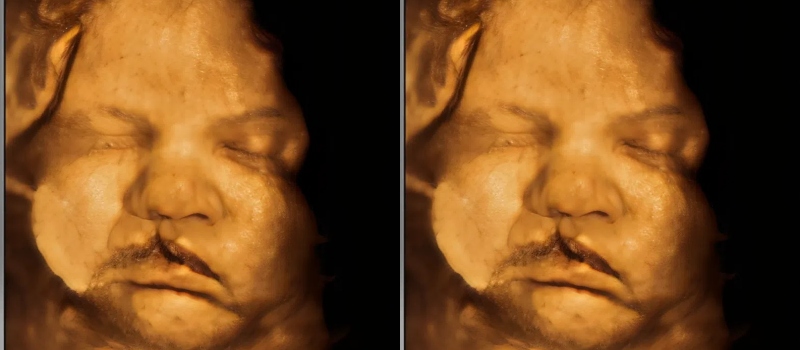

The second image arrived weeks later, replacing uncertainty with clarity. Orion’s face was clearer now, pressing forward as if listening through glass. His mouth curved in an unfamiliar way—not wrong, just different, like a sentence that pauses where you don’t expect it to. Mara’s partner, Elias, squeezed her hand and stayed silent, which was his way of saying everything.

The third image came from a machine that hummed like a thoughtful animal. It showed Orion before he learned air, before gravity explained itself to him. In grayscale, he looked ancient, like a memory the world had borrowed. A technician pointed out bones and contours mapping themselves with patient logic. Mara imagined Orion listening in the dark, practicing expressions he would one day need. She wondered whether faces were rehearsals or revelations. When the screen went black, the room felt smaller, as if the future had leaned in close and then stepped back 👶.